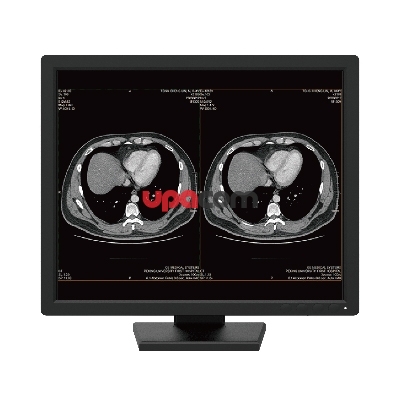

Отображение рентгеновских изображений и изображений в поперечном разрезе является основной задачей RX250. Благодаря характеристической кривой DICOM GSDF она может точно отображать радиологические экспозиции.

Отображение рентгеновских изображений и изображений в поперечном разрезе является основной задачей RX250. Благодаря характеристической кривой DICOM GSDF она может точно отображать радиологические экспозиции.

Функция CAL Switch позволяет вам выбирать различные режимы для различных модальностей, таких как CR, CT и эндоскопия. Его можно легко получить с помощью кнопок на передней панели монитора, чтобы легко переключаться на оптимальные условия просмотра изображений.

Опыт плавного воспроизведения цвета

Монитор поддерживает 10-битный вход для каждого цвета RGB, отображая одновременно более одного миллиарда цветов. Это обеспечивает точную цветопередачу для 3D-рендеринга и слияния изображений.